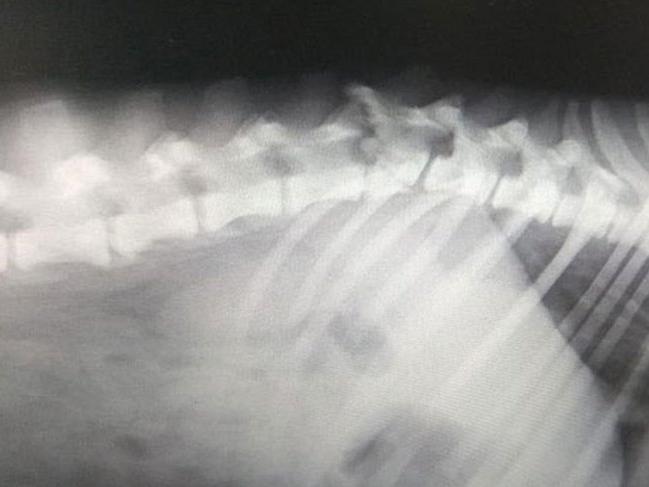

FOTO: DHAŞiddet mağduru köpeğin tedavi edilmesi için mücadele eden HİPDER üyeleri, veterinerlerden ameliyatın çok pahalı olduğunu ve ameliyat gerçekleşmezse hayatına bu şekilde devam etmek zorunda kalabileceği bilgisini aldı. Sokakta felç bir halde yaşayamayacağını söyleyen dernek üyeleri, köpeğin sahiplendirilmesi için çağrıda bulundu.

Son birkaç gündür benzeri 5- 6 olayla karşılaştıklarını söyleyen HİPDER Başkanı Funda Bonomo, köpeğe gerekli tedavilerin uygulandığını fakat omurgasındaki sinirlerin tümünün ezildiğini, bu şekilde ancak sahiplenirse iyi bir hayatı olabileceğini belirterek, hayvanseverlere çağrıda bulundu.